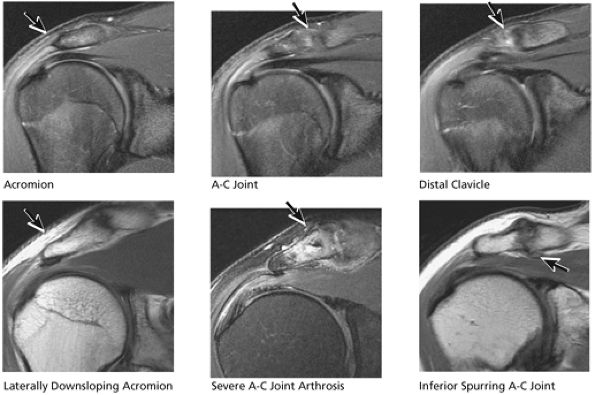

FIGURE 8.33 Acromioclavicular Joint.